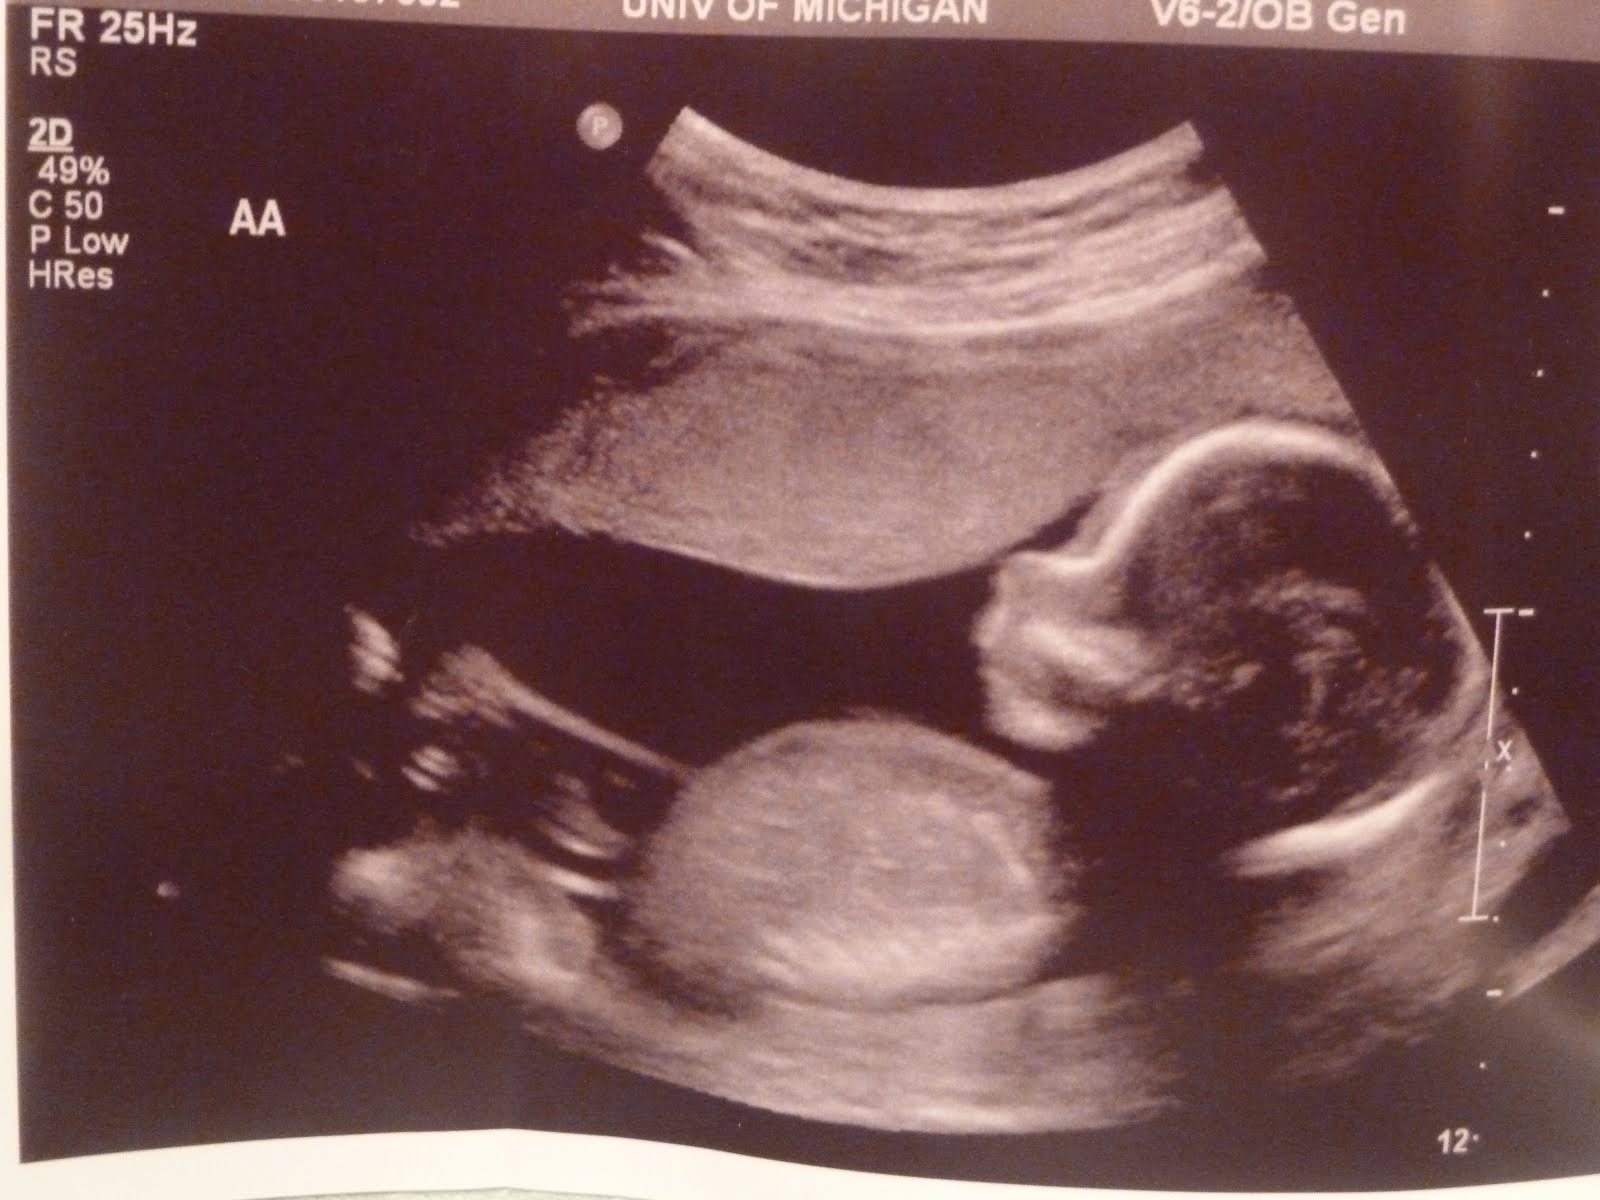

УЗИ на 19 неделе беременности является важной процедурой, позволяющей увидеть малыша внутри матки и определить его пол. Если вы интересуетесь, как выглядит ребенок на этом сроке, вам точно понравятся эти фотографии.

Фотографии узи на 19 неделе беременности

На этом сроке беременности ребенок уже достаточно развит, чтобы можно было увидеть его пол при помощи ультразвукового исследования. Ваш врач или специалист по УЗИ сможет провести исследование и показать вам ясные и детальные изображения малыша.